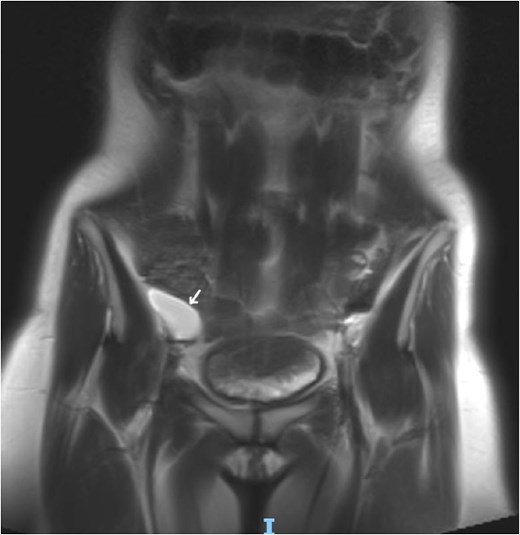

Laboratory studies, including complete blood count and comprehensive metabolic panel, were within normal limits. Initial ultrasonography (US) revealed an oblong cystic lesion with fine septations, measuring 6.5 × 3 cm, extending through the right inguinal canal into the labium majus (Figs 1 and 2). Subsequent pelvic magnetic resonance imaging (MRI) corroborated these findings, demonstrating a right lower abdominal cystic lesion with thin septations extending to the inguinal region, showing low T1 and high T2 signal intensity, measuring ~7 × 3.5 cm (Figs 3 and 4). No evidence of bowel or omental herniation was observed, suggesting canal of Nuck hydrocele.

Axial MRI view of the pelvis, showing the extension of the cyst into the right inguinal canal with no bowel or omental herniation (arrow).